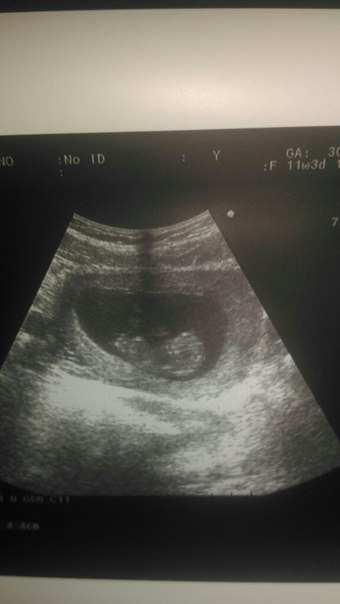

Результаты: УЗИ, КТГ, доплера, скринингаНаконец-то по узи мне поставили срок 11,5 недель, вчера гинеколог из ЖК решил что у меня 9 недель, забавно конечно, но даже при таких подсчетах на скрининг я прохожу хорошо в 13,5 недель (13 июля). Зато теперь считаю срок беременности идеально и верно 100%))))

Какое же это счастье, просто невозможные слезы умиления, когда ты видишь этот маленький долгожданный комочек, это закрашенное серое пятнышко на мониторе и понимаешь что это твой ребенок, твой самый настоящий человечек! Это поистине божественные ощущения усиливаются, когда врач включает прослушивание ударов сердца...и полный восторг и апогея всего узи, когда малыш машет ручкой!

Уже сейчас до скрининга ясно что паталогий тьфутьфутьфу нет, еще позже добавлю расшифровку замеров.